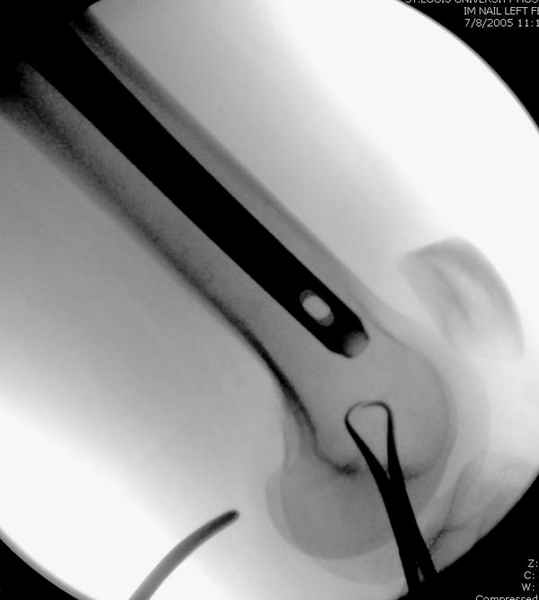

Как раз недавно у меня был примерный случай: больному 36 лет, поступил ночью, травма в результате мотоциклетной аварии, кроме чрезвертельного и спирального перелома левого бедра имеется переломы костей предплечья с этой же стороны. Скелетное вытяжение, а на следующий день больной про оперирован на ортопедическом столе с дистракцией. Чтобы не расколоть чрезвертельный перелом провели временную спицу ближе к переднему кортексу, из малого разреза костодержатель для репозиции, а фиксацию провели антиградным штифтом. Этапы операции на снимках.

Джолдас Кульджанов